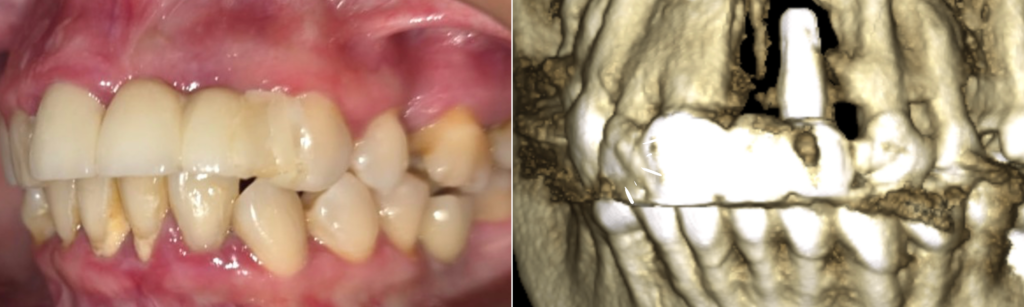

El diagnóstico fue periimplantitis severa. Esta enfermedad infecciosa afecta a los implantes convencionales y provoca una destrucción progresiva del hueso que los sujeta. Como se puede apreciar en las imágenes 3D de nuestro diagnóstico, no quedaba hueso en contacto con el implante, que se mantenía en boca únicamente porque estaba cementado a un diente natural vecino.

En estos casos, las técnicas de regeneración ósea convencionales no son viables. La ausencia total de paredes óseas hace que la regeneración sea de dudoso éxito, implicaría cirugías complejas, muchos meses de espera y, lo que es más importante, el paciente tendría que pasar todo ese tiempo sin un diente provisional.

1. Anclaje en Hueso de Calidad: A diferencia de los implantes convencionales, que dependen del hueso alveolar (el que se destruyó), los implantes córticobasales se anclan en el hueso cortical basal, una zona más profunda, densa y libre de infección. Esto los hace ideales para casos con pérdida ósea severa.